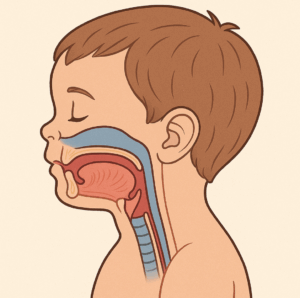

ご存知かもしれませんが、口呼吸ではこの2つが悪い状態になる傾向があります。背景にあるのは顔(あご)の成長不足が起こるからなのですが、それにより並ぶ場所が狭いために歯並びまで悪くなるのです

(AI作成)

(AI作成)